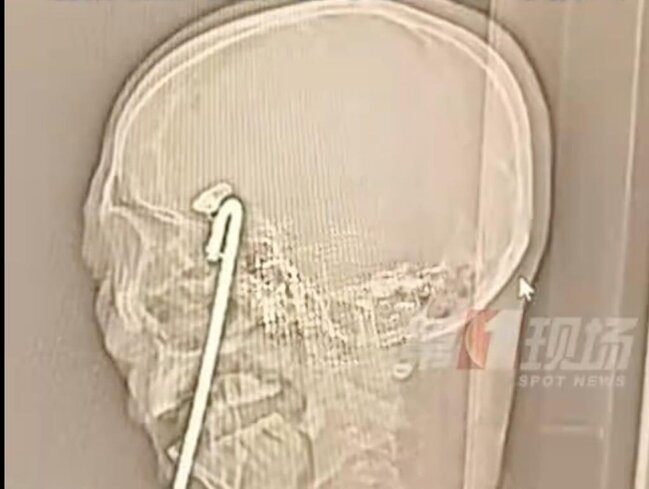

Hadisə Guangdong əyalətində yerləşən Şenzhen Universiteti Ümumi Xəstəxanasında qeydə alınıb. "Aqiang" təxəllüsü ilə tanıdılan kişi həmkarları ilə birlikdə yemək yeyərkən sərxoş olub, ayağa qalxarkən tarazlığını itirərək masanın üzərində dik vəziyyətdə olan 40 sm uzunluğundakı metal çubuğun üzərinə yıxılıb. Çubuq onun ağzından daxil olaraq beyninə qədər irəliləyib.

Travma Mərkəzinin həkimləri hadisəni nadir və son dərəcə təhlükəli adlandırıblar. Onların sözlərinə görə, çubuq ağız, göz və beyin nahiyəsindən keçib və uc hissəsi beynin əsas qan damarlarına cəmi 2 mm məsafədə dayanıb.

Əməliyyata başlamazdan əvvəl həkimlər çubuğun xaricdə qalan hissəsini diqqətlə kəsiblər. Əməliyyatın ən çətin hissəsi çubuğun ucundakı metal klipi zədələmədən çıxarmaq olub. Həkimlər hər hansı bir yanlış hərəkətin ölümə səbəb ola biləcəyini bildiriblər.